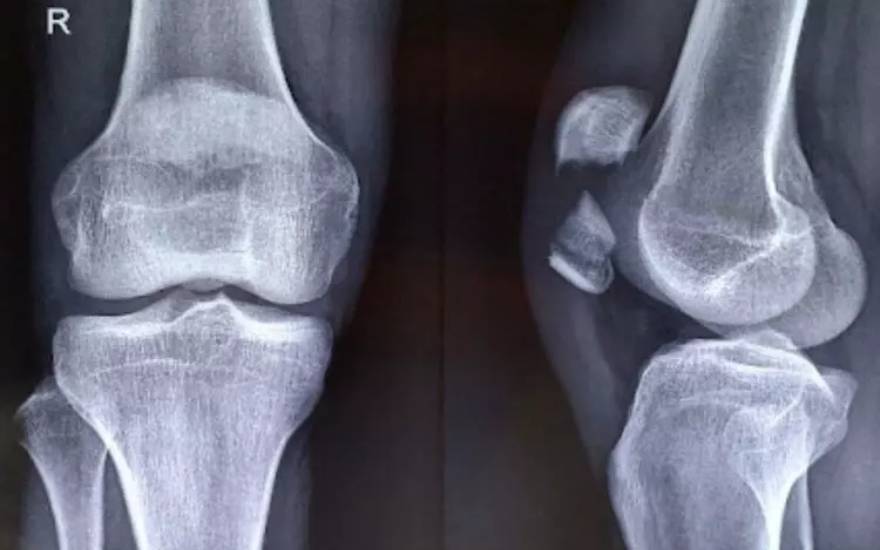

手术复位内固定

在髌骨严重粉碎、明显移位或出现游离骨块的情况下,手术治疗是更为有效的选择。医生会通过骨折复位内固定手术,将分离的骨折块重新对位并牢固固定,以恢复髌骨的正常结构和功能,从而降低日后发生关节错位或活动功能障碍等并发症的风险。

严重髌骨骨折通常需要通过手术进行骨折内固定治疗